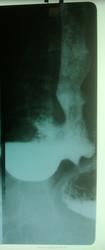

ГПОД.

У меня складывается впечатление, что свод желудка на месте. Но есть недостаточность кардии и огромный дивертикул в наддиафрагмальной части пищевода.( Это так, брожение ума. Недостаточно снимков)

+1. И у меня такое же мнение. По данным ФГДС- ГПОД. Но по мне так больше на дивертикул похож.

Гигантский дивертикул...и знаете почему такой вывод - если ТАКАЯ грыжа ПОД, то где деформация ОСТАЛЬНОЙ части желудка, он то НОРМАЛЬНОЙ формы...вот собственно где то так

По классификации -это эпифренальный дивертикул, может быть большим, клиника тоже может быть длительно невыраженой...разве что присоединится дивертикулит, тогда - "зазвучит".

Это обычно пульсионные дивертикулы наддиафрагмального и, редко, ретроперикардиального сегментов пищевода.

"Почти половина эпифренальных ДП выявляется случайно, как рентгенологическая находка. Обычно это дивертикулы диаметром до 2 — 3 см..... Клинические проявления больших дивертикулов связаны с раздражением блуждающего нерва и сдавленней передней стенки пищевода, что проявляется дисфагией, тяжестью за грудиной, иногда чувством остановки пищи, срыгивапиями, какосмией, тошнотой. Спазм стенок пищевода или кардиоспазм вызывает боли после еды, регургитацию, а иногда и пищеводную рвоту. По мере увеличения размеров эпифрепальных ДП появляются одышка, сердцебиение и боли в области сердца без изменений на ЭКГ (псевдостенокардия Фурнье), симптом «булькающего желудка» за грудиной, гнилостный запах изо рта и др."